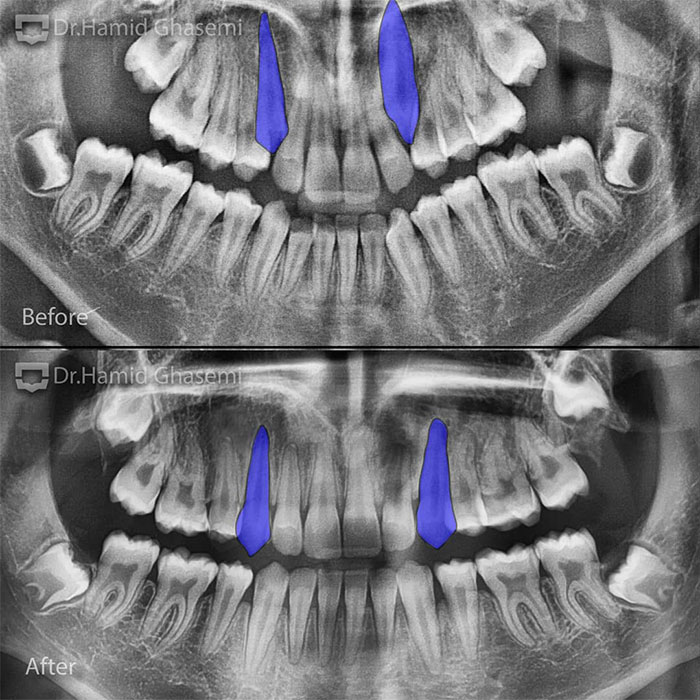

درمان ارتودنسی در کیس همراه با دندانهای نیش نهفته فک بالا در هر ۲ طرف در مدت ۲۴ ماه انجام شد.

Orthodontic treatment of case with impacted upper canines on both sides done within 24 months.